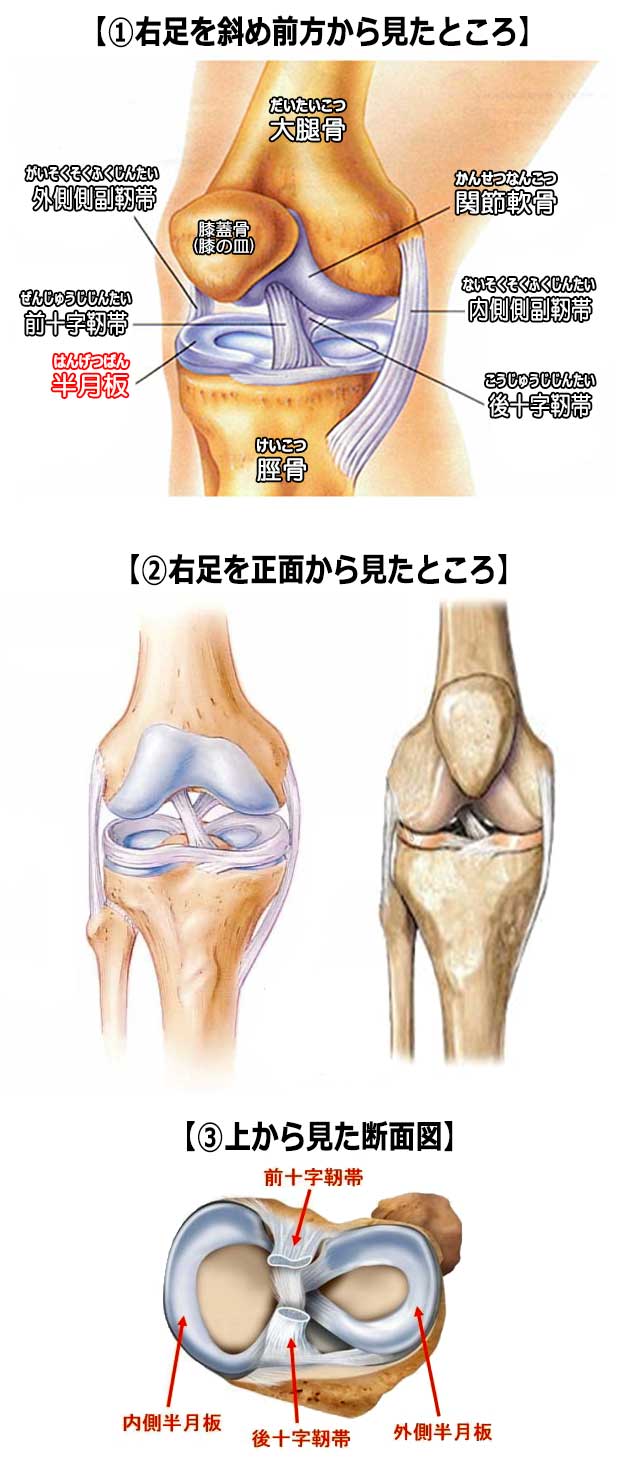

イラスト図解 ひざ関節 足 下半身の構造 骨 筋肉 靭帯 腱の名称や働き

膝 の構造を理解して自然な表現を心がけよう 美少女イラストのリアルな肌の塗り方 第9回 Pictures

イラスト図解 ひざ関節 足 下半身の構造 骨 筋肉 靭帯 腱の名称や働き

イラスト図解 ひざ関節 足 下半身の構造 骨 筋肉 靭帯 腱の名称や働き

イラスト図解 ひざ関節 足 下半身の構造 骨 筋肉 靭帯 腱の名称や働き

画像 ひざ関節の解剖図 前後 看護ノート 解剖学 筋肉解剖学